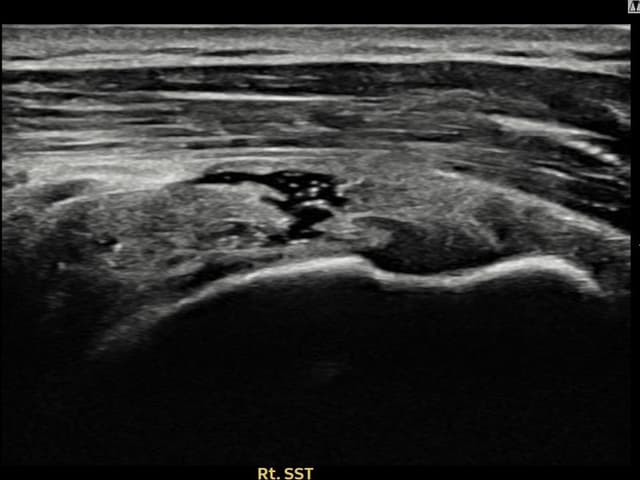

実際の患者様の施術前後の超音波画像。

手術なしで実現できる回復をご確認ください。

[経過期間: 23.10.05~23.12.07]

[縫縮術] 超音波検査にて右 棘上筋腱 付着部部分断裂(10mm × 4mm (腱厚の約42%欠損))を確認。縫縮術施行後、腱の連続性が回復し、日常生活に復帰されました。